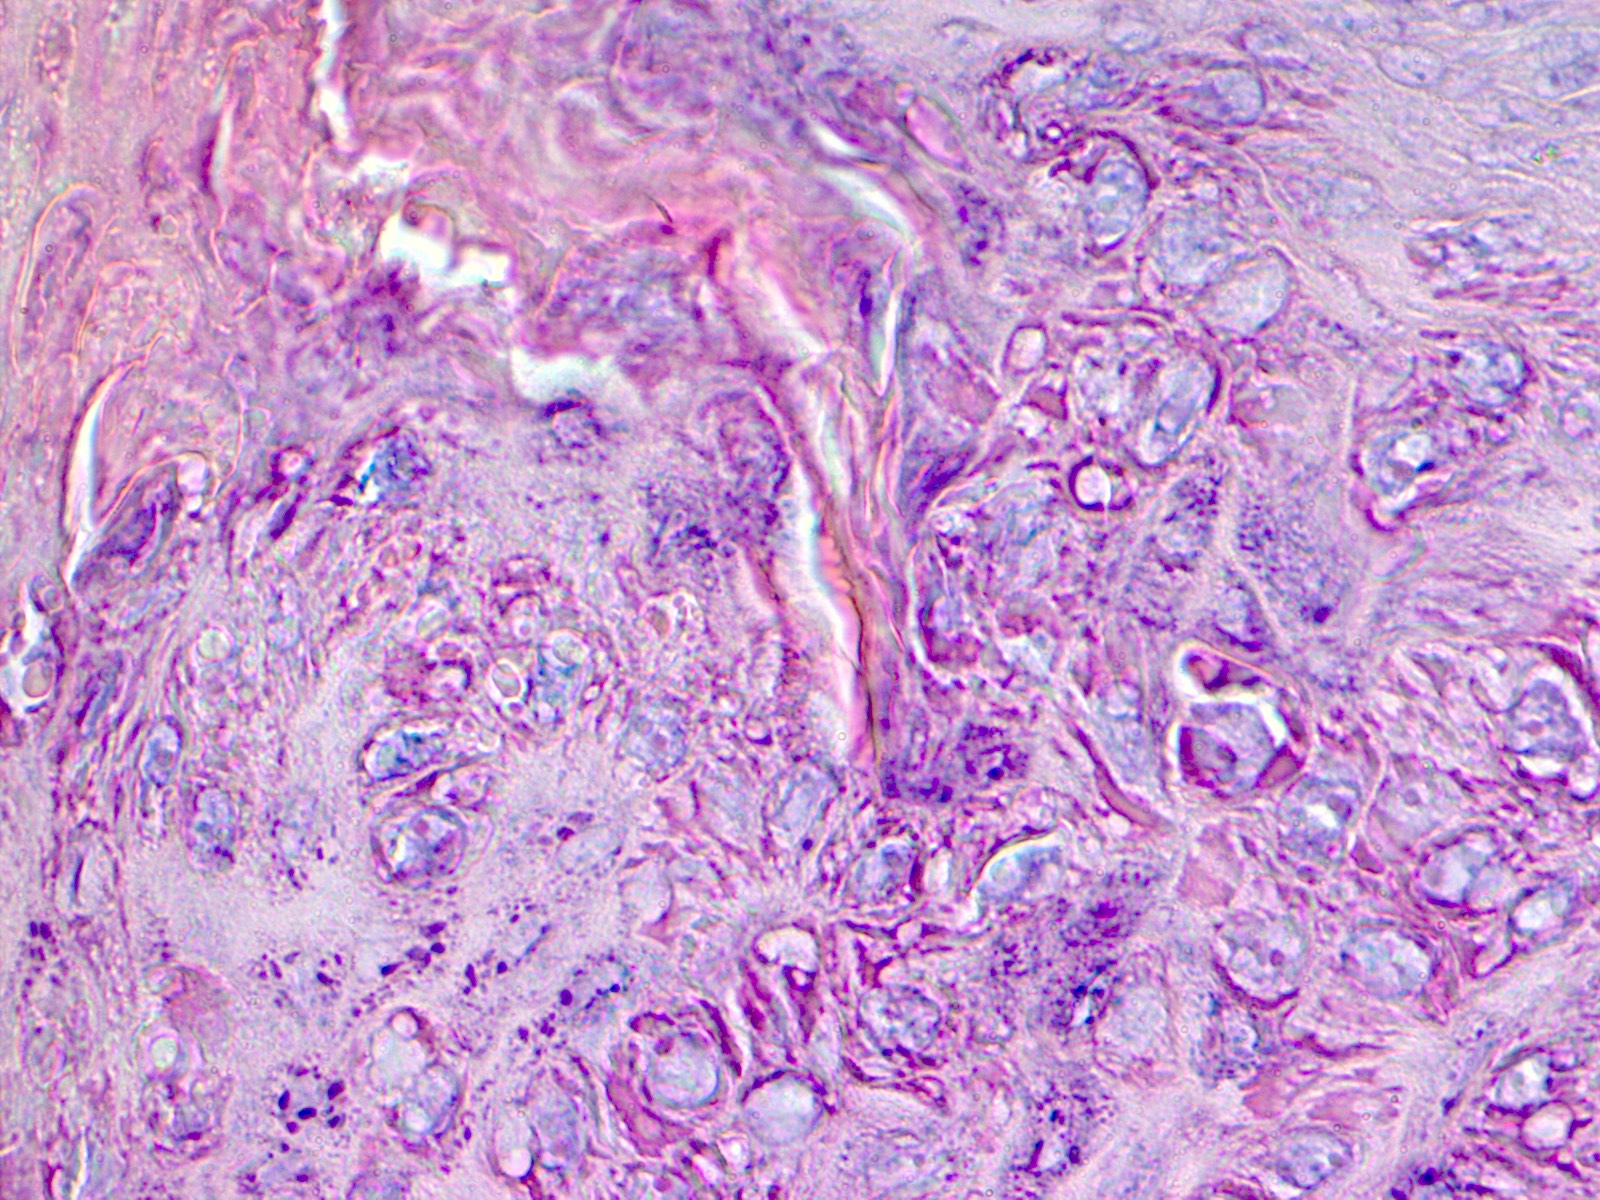

- Palmar / plantar warts (verruca palmaris and verruca plantaris) (Arch Pathol Lab Med 2018;142:700):

- Similar to verruca vulgaris (clinical distinction based on location)

- Endophytic growth - greater proportion of the lesion lies beneath the plane of the epidermis

- Myrmecia warts (J Cutan Pathol 2012;39:936):

- Marked acanthosis

- Large eosinophilic intracytoplasmic inclusion bodies

Microscopic (histologic) images

Contributed by Heba Ahmed Abdelkader, M.D., Hillary Rose Elwood, M.D., AFIP,

@MirunaPopescu13 on Twitter and @shilpa_rakesh_path on Instagram